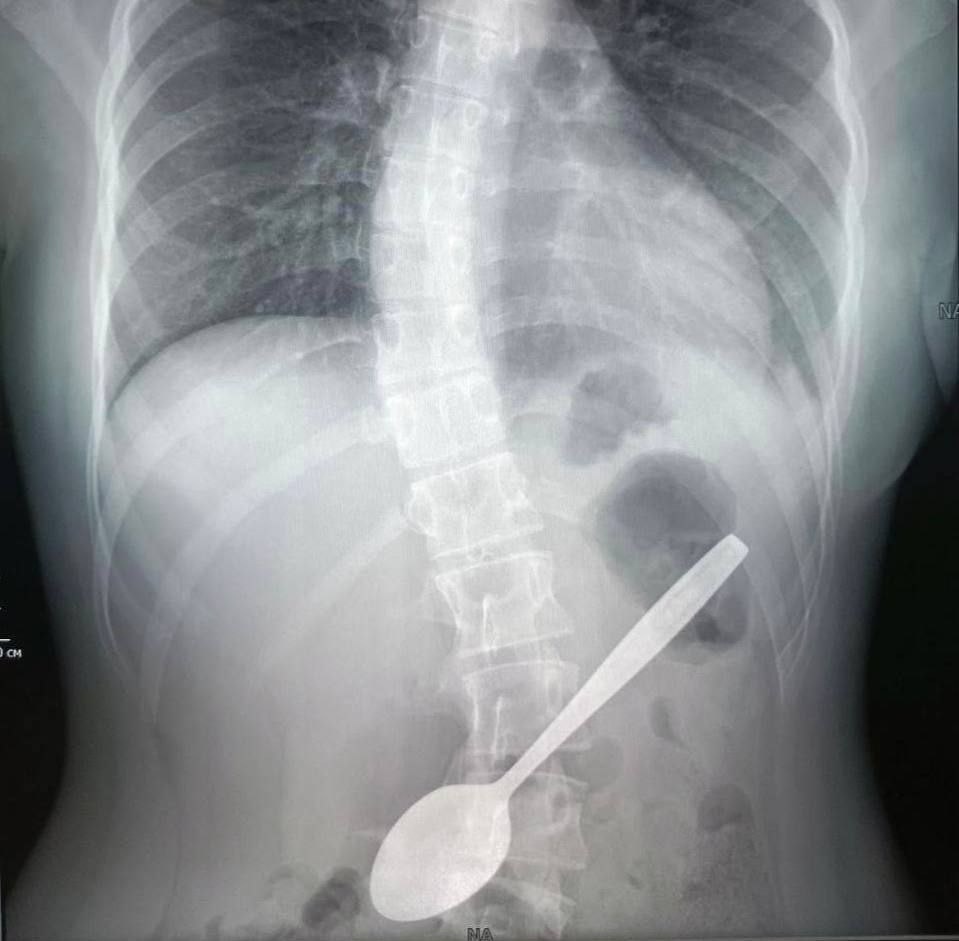

Школьница из Подмосковья случайно проглотила чайную ложку. Девочка проглотила 15-сантиметровую ложку, когда пыталась достать кусок яблока, застрявший у неё в горле. Со столовым прибором в желудке её доставили в хирургическое отделение Центра Рошаля. Врачи сделали рентген и извлекли предмет.

Со столовым прибором в желудке её доставили в хирургическое отделение Центра Рошаля. Врачи сделали рентген и извлекли предмет.